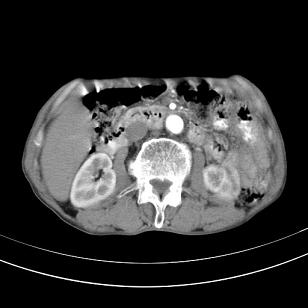

标题: 男,65岁,反复右上腹痛, [打印本页]

标题: 男,65岁,反复右上腹痛,

胃镜提示十二指肠占位